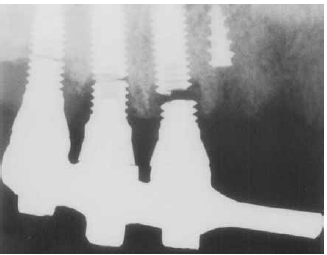

Elias, Ducos e Andrade. Análise da fratura de

implante. In: Revista brasileira de implantodontia, out.-dez./2006, p. 5-8 (com adaptações).

A figura acima mostra um material de implante dentário que sofreu um processo de fratura. Para se avaliar a resistência desse material à fratura deveria ter sido empregado o ensaio